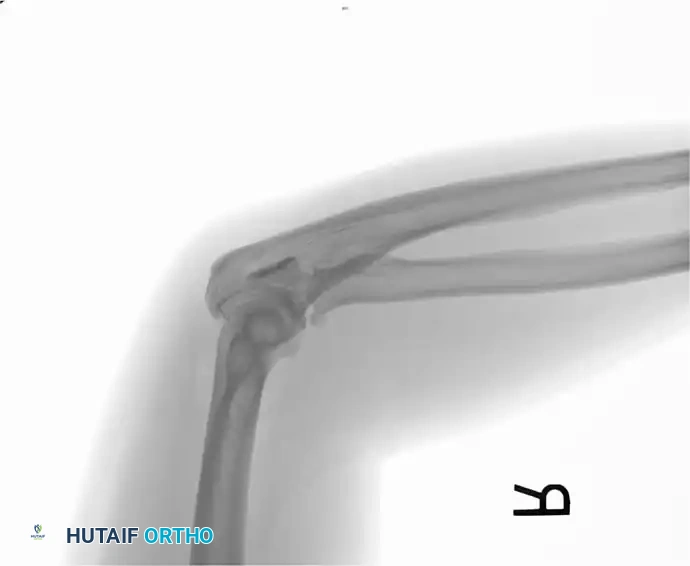

1. Direct Trauma: A direct blow or fall onto the tip of the elbow. This mechanism frequently results in comminuted fracture patterns and significant articular cartilage damage.

2. Indirect Trauma: A fall onto a partially flexed elbow accompanied by a sudden, forceful contraction of the triceps muscle. This indirect force avulses the olecranon, typically resulting in a transverse or oblique fracture pattern with a clean articular break.